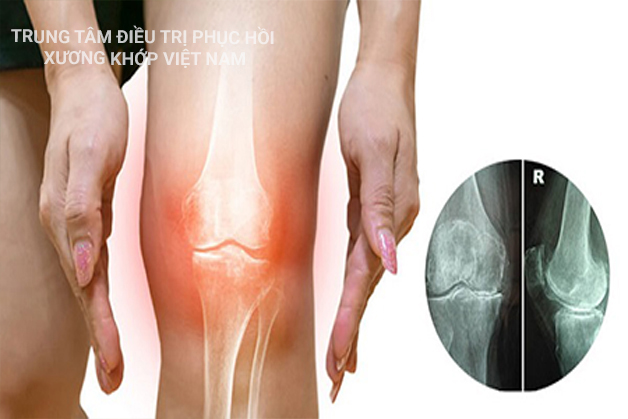

1. Tình trạng bệnh xương khớp tại Việt Nam   Cấu tạo cơ xương khớp cơ thể người (Ảnh minh họa)   Hiện tại, Việt Nam đang là một trong những nước phát triển với tỷ lệ người mắc ...